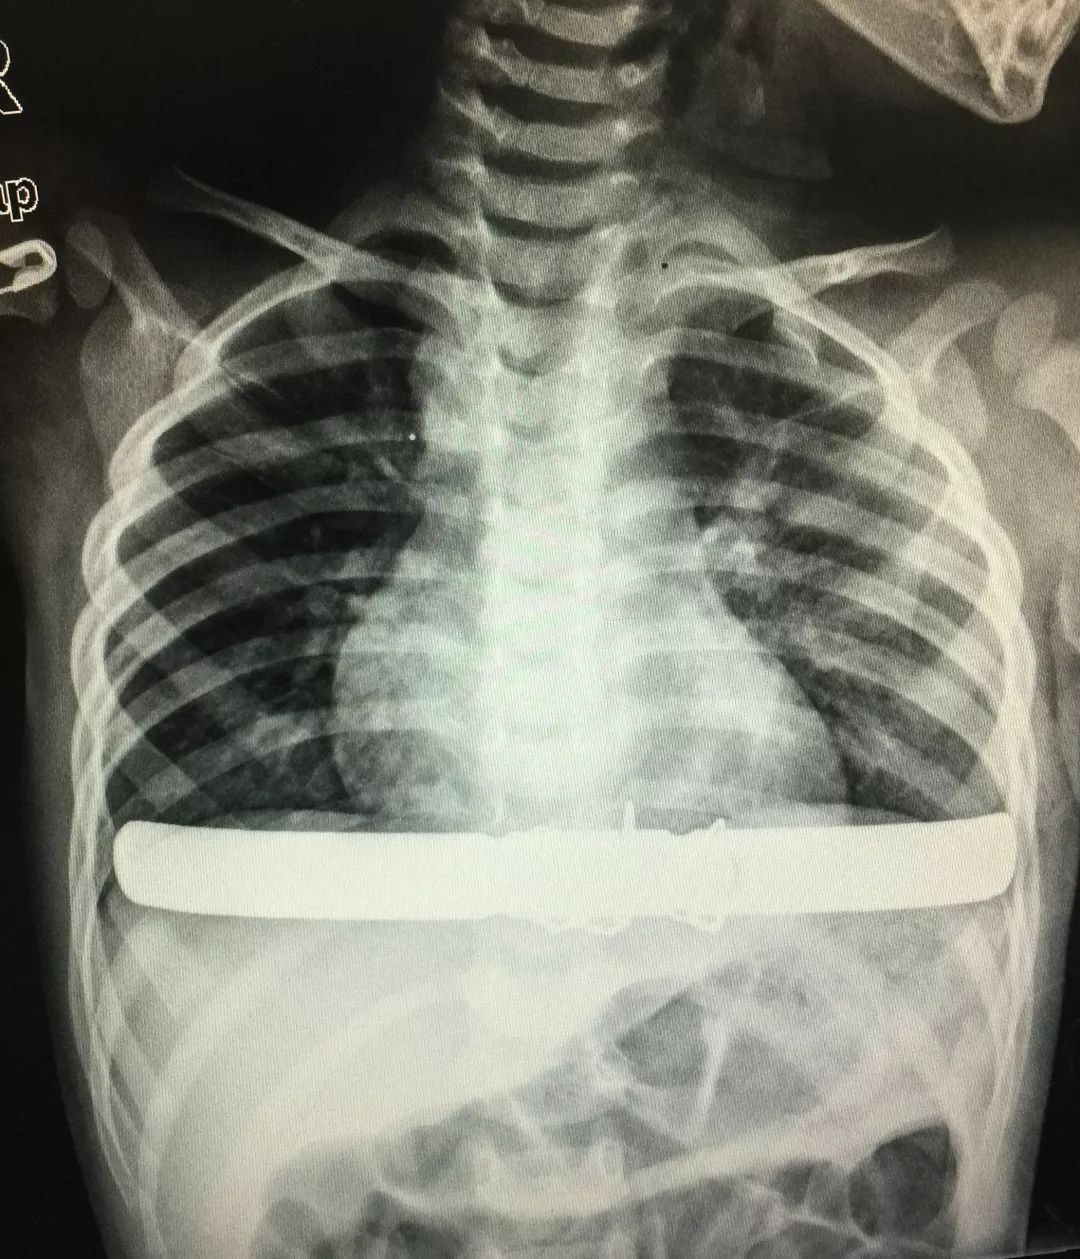

术后患儿胸壁塑形良好,漏斗胸完全消失,患儿康复快速,于术后第4天顺利出院。

术后